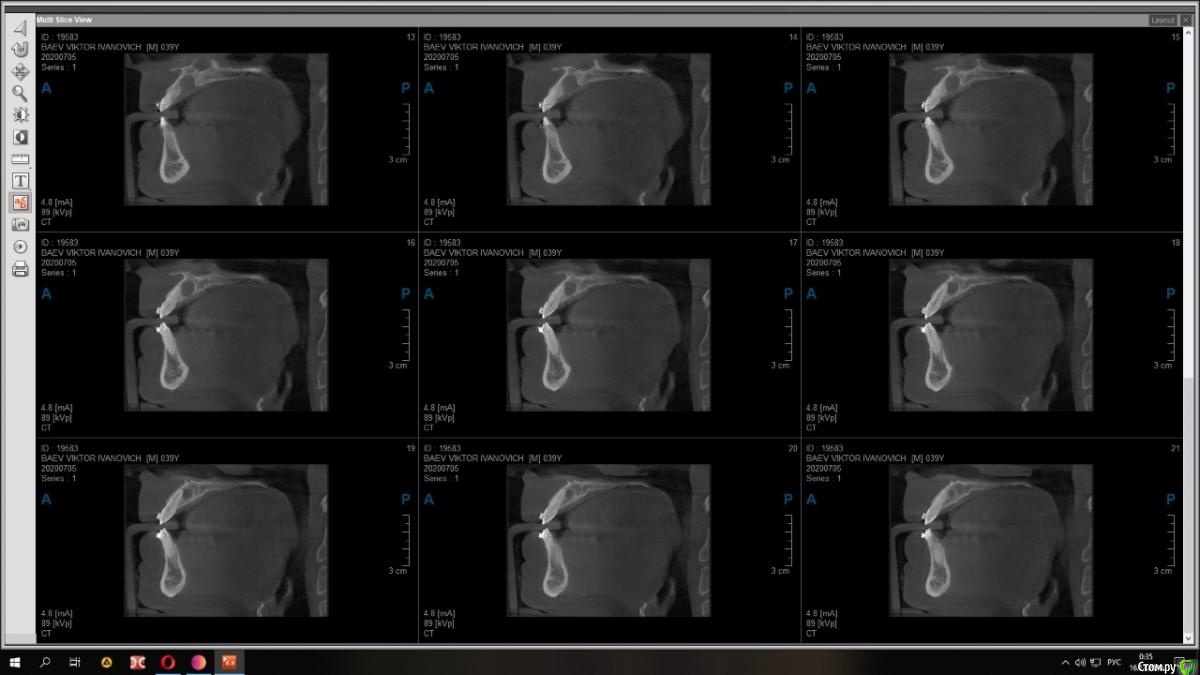

Raystom Опубликовано 18 декабря, 2020 Автор Поделиться Опубликовано 18 декабря, 2020 Срезы из других проекций Ссылка на комментарий

bilal Опубликовано 19 декабря, 2020 Поделиться Опубликовано 19 декабря, 2020 c чего вы решили что киста. как будто расширенный канал просто Ссылка на комментарий

Raystom Опубликовано 21 декабря, 2020 Автор Поделиться Опубликовано 21 декабря, 2020 c чего вы решили что киста. как будто расширенный канал просто ну не, это 80 процентов она Ссылка на комментарий